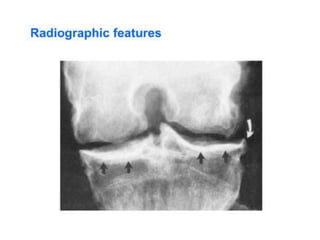

HPOA:

• Clubbing + arthralgia with joint swelling of

wrists and ankles

• X-rays show subperiosteal new bone formation

Right ankle

radiograph

demonstrating

periosteal

reaction along

distal tibial

and fibular

diaphysis

(arrows).